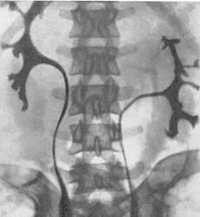

(Слева) Другой случай. Аутопсия. Почки сращены и лежат по одну сторону от аорты. Мочеточник эктопической почки пересекает срединную линию и впадает в мочевой пузырь в типичном месте.

(Справа) УЗИ плода в 36 нед., фронтальная плоскость. Лоханка правой почки расширена. Обе почки лежат с одной стороны. Над мочевым пузырем меньшая из них (левая) примыкает к нижнему полюсу правой.